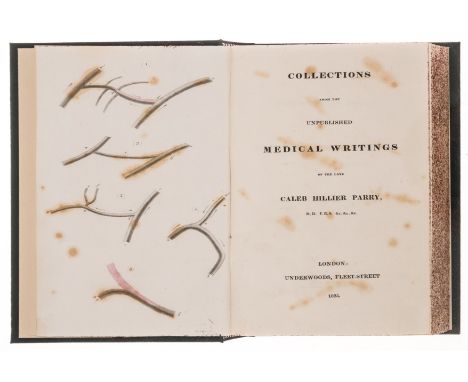

Parry (Caleb Hillier) Collections from the Unpublished Medical Writings..., 3 vol., only edition, errata slip and advertisement leaf at end of vol.1, vol.3 with partly hand-coloured engraved plate (foxed and offset onto title), ex-library set with ink stamps to titles of vol.1 & 2 but removed from that of vol.3, otherwise a good clean copy, modern cloth, together in slip-case, [Wellcome IV, 310], 1825 § Robinson (Bryan) Observations on the Virtues and Operations of Medicines, first edition, one folding engraved plate printed in sepia, tables, light marginal water-staining, contemporary half calf, rubbed, rebacked, J.Nourse, 1752 § Heberden (William) Commentaries on the History and Cure of Diseases, first American edition, ink signature to head of title, foxed, modern bookplate of Eric Bywaters, contemporary sheep, a little worn, Boston, 1818; and 11 others, medicine, 8vo (16)⁂ The first item is one of few works by Parry, edited posthumously by his son and including the rare third volume 'Introductory Essays by Charles Henry Parry'. Parry is known for his work on angina pectoris and, particularly, exophthalmic goitre.